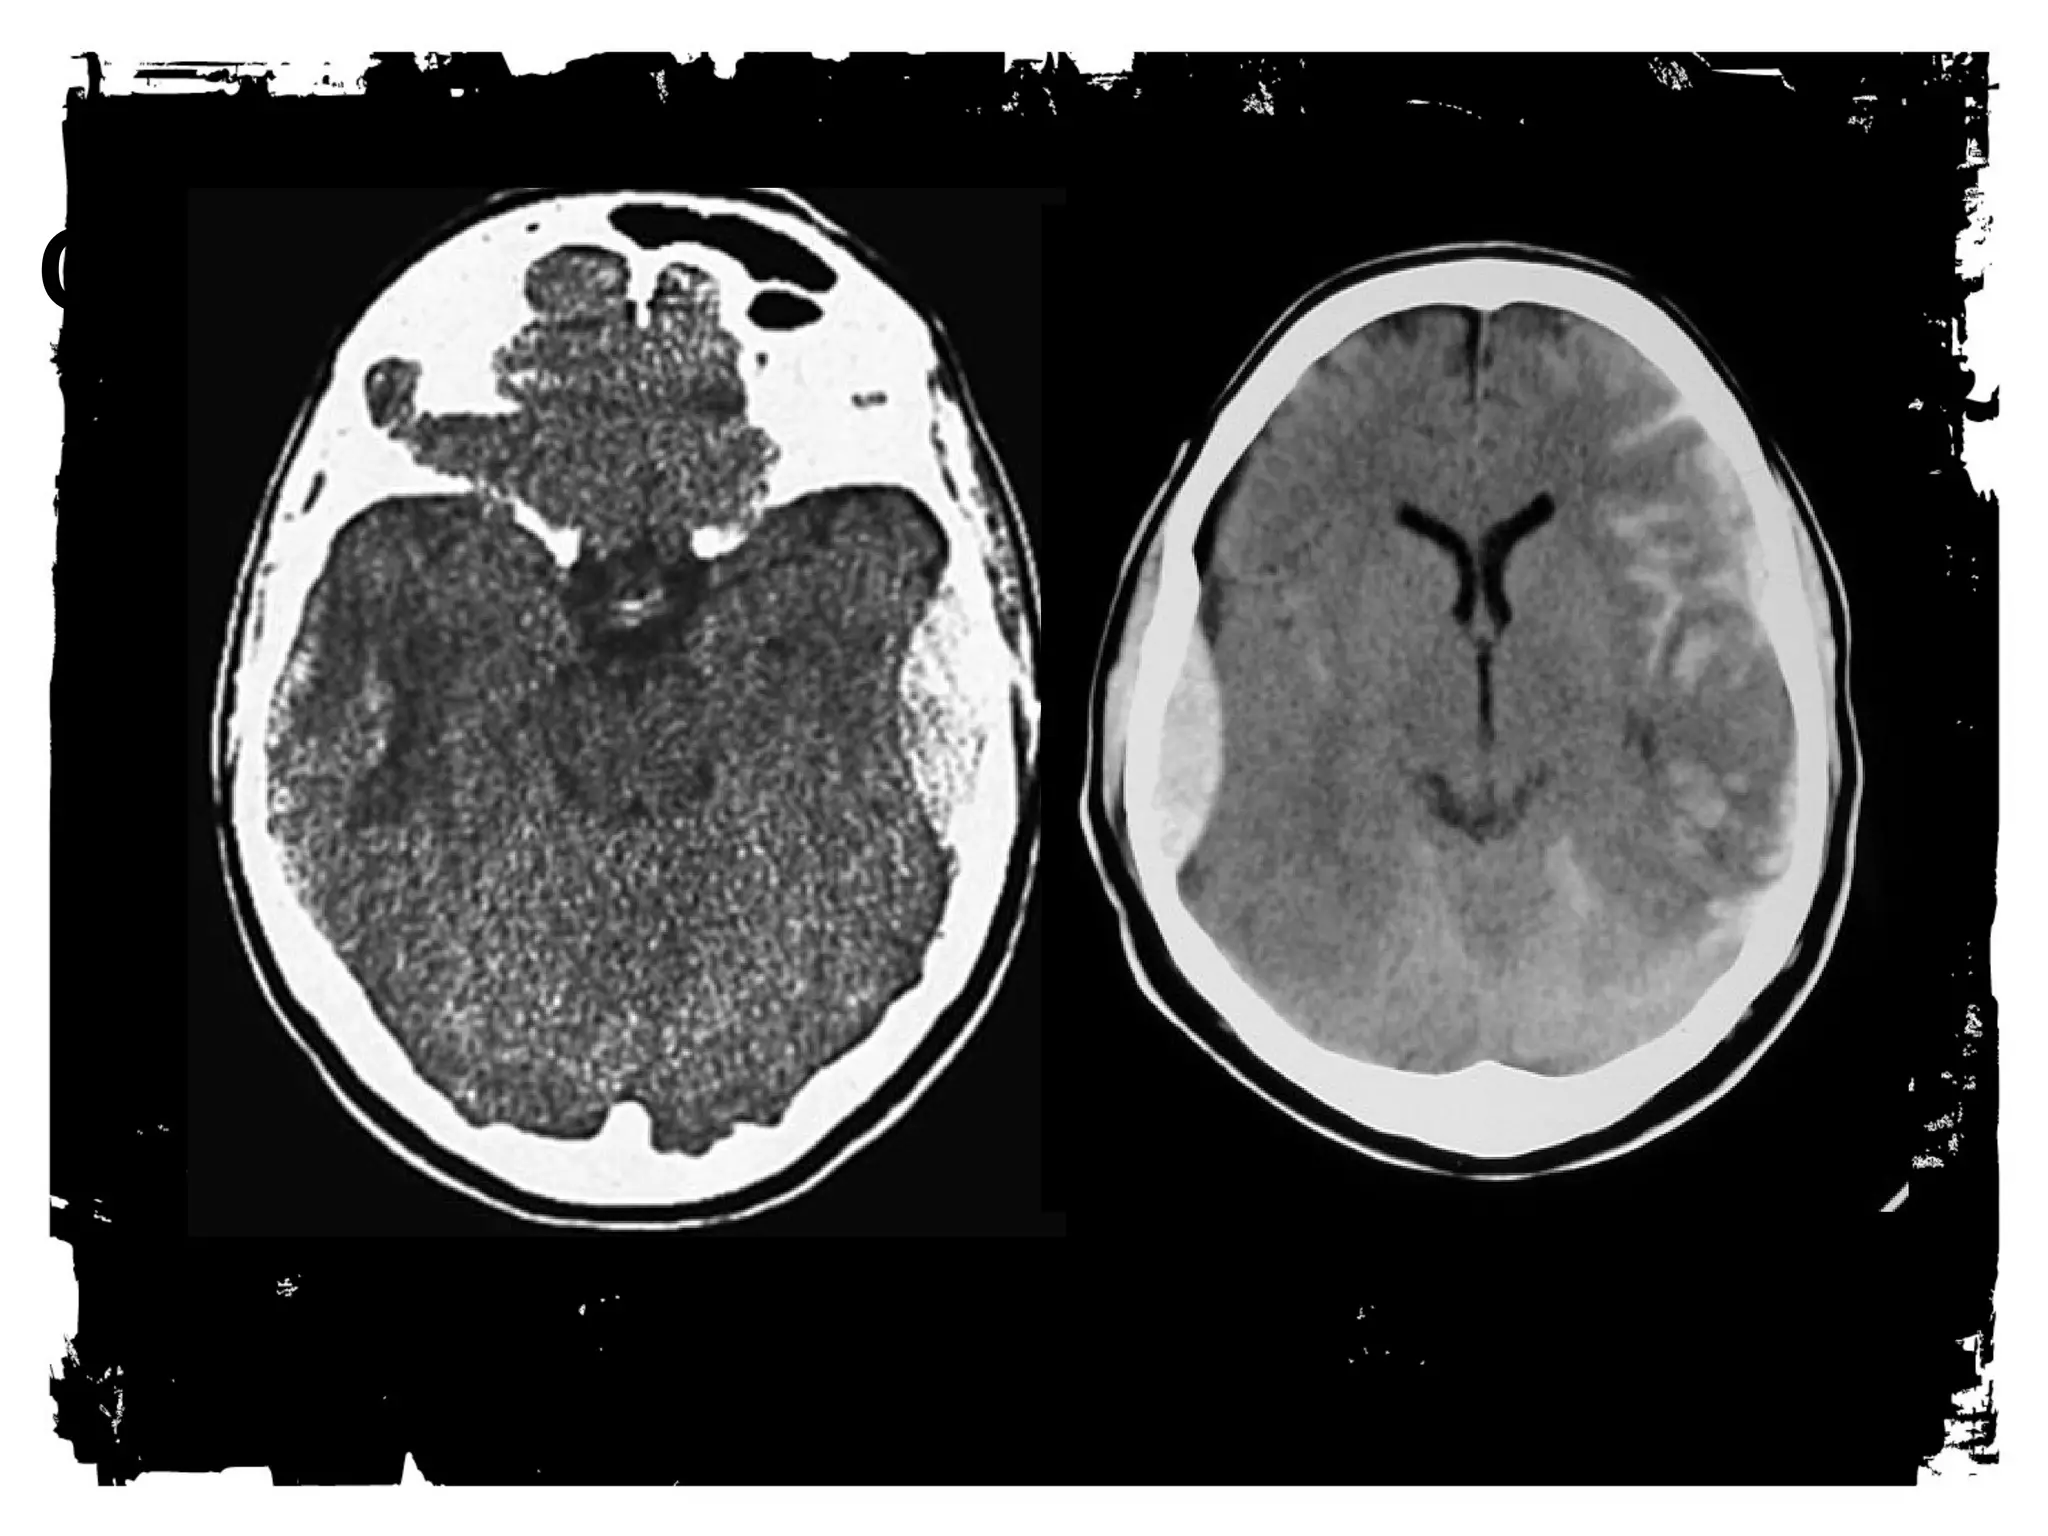

Head CT

Advantages for TBI include: availability, short scan times,

detailed anatomic information - including evaluation of facial

and temporal bone fractures.

Less sensitive for small parenchyma bleeds such as those seen

with DAI.

CLICK Anatomic HPaEttRernEs Tof O ADD TEXT

Traumatic Brain injury

BBlloooodd: eeppiidduurraall,, ssuubbdduurraall,, ppaarreenncchhyymmaa,, vveennttrriiccuullaarr,,

aanndd ssuubbaarraacchhnnooiidd..

DDiirreecctt iinnjjuurryy ttoo bbrraaiinn –– ffrroonnttaall lloobbee aanndd aanntteerriioorr

tteemmppoorraall lloobbee..

SShheeeerriinngg iinnjjuurryy: ddeeffoorrmmaattiioonn ooff bbrraaiinn ccaauussiinngg ddiiffffuussee

aaxxoonnaall iinnjjuurryy..

Among patients eventually

proven to have DAI, 50-80%

demonstrate a normal CT scan

upon presentation. Delayed CT

scanning may be helpful in

demonstrating edema or

atrophy, which are later

findings. Small petechial

hemorrhages located at the

gray-white matter junction, as

well as in the corpus callosum

and brainstem, are

characteristic of CT-scan

findings in the acute setting.